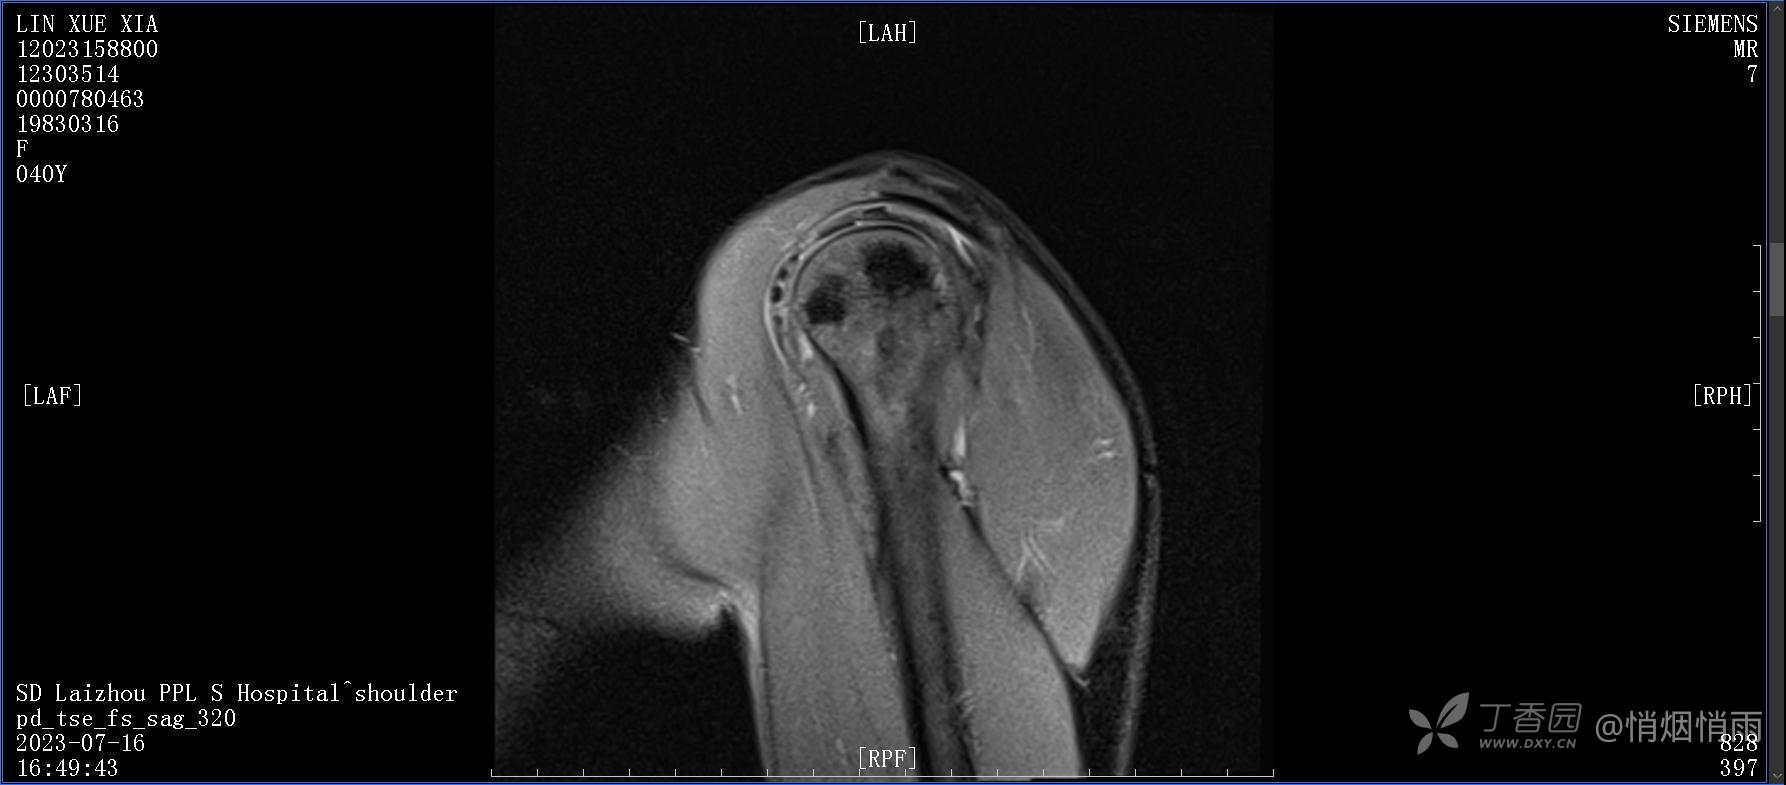

查体:右肩关节局部轻度肿胀,肩胛区压痛明显,痛处不固定,肩关节痛性活动受限,jobe test(+),lift -off test(+),中指、环指感觉较余指减退,余肢端感觉及血运情况可。

目前的诊断,暂时依据辅助检查诊为肩袖损伤,但是患者疼痛的性质和特点,却不是单纯的肩袖损伤所致。考虑过胸廓出口综合征,但是该疾病会出现肩胛区的疼痛吗?(由于考虑到费用的问题,没再进行下一步的检查)带状疱疹会有如此的症状吗?